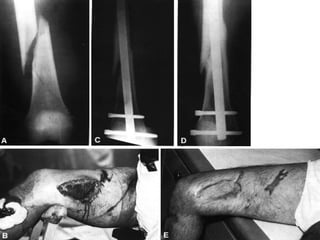

FRACTURA EXPUESTA Es la perdida de continuidad ósea, en  la que el foco de fractura se pone en contacto con el medio ambiente

PARAMETROS DE CLASIFICACION Medio ambiente en que sucedió Tiempo transcurrido entre la lesión y el tratamiento hospitalario El grado de lesión de las partes blandas del miembro afectado o áreas circunvecinas

CLASIFICACION DE LAS FRACTURAS EXPUESTAS Contaminadas : < de 6 hrs de evolución, contaminación por gérmenes del medio ambiente o el agente agresor Infectadas : > de 6 hrs de evolución, reproducción de los gérmenes localmente Complicadas : es la que se acompaña de lesiones en órganos, sistemas, o elementos anatómicos vecinos

CLASIFICACION Las clasificaciones complementarias se basan en el grado de lesión de partes blandas, siendo la mas utilizada la de Gustilo

CLASIFICACION DE GUSTILLO I:  Herida < 1 cm. Herida limpia realizada por un fragmento puntiagudo de hueso que perfora la piel, existe escasa lesión a tejidos blandos, sin signos de aplastamiento, son por baja energía

CLASIFICACION DE GUSTILLO II:  Longitud > 1 cm. Sin colgajos, avulsiones y sin una gran lesión de tejido blando, existe un mínimo a moderado aplastamiento, conminución y contaminación moderada

CLASIFICACION DE GUSTILLO III:  Lesión extensa de tejidos blandos que afectan al músculo, piel y estructuras neurovasculares, suele existir un alto grado de contaminación, son por alta energía A)  cobertura adecuada de tejido blando del hueso, sin importar el tamaño de la herida

CLASIFICACION DE GUSTILLO B)  Afectación extensa o perdida del tejido blando con exposición del hueso, contaminación masiva y una grave fractura conminuta C)  Se asocia a lesión arterial  que necesita reparación independientemente del grado de lesión del tejido blando